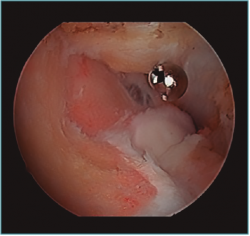

Acto seguido, realizamos nuestra secuencia de trabajo descrita anteriormente (visualización, creación de espacio, trabajo óseo y trabajo de partes blandas). El fresado óseo debe realizarse siempre con el instrumental motorizado orientado hacia el húmero, para evitar las lesiones de partes blandas. El uso de fresas o el sinoviotomo en modo no oscilante y a alta velocidad nos permitirá eliminar los osteofitos que interfieran con la movilidad, especialmente aquellos que ocupan la fosa radial o coronoidea (Figura 8). También es frecuente tener que eliminar osteofitos que aumentan la altura de la coronoides (Figura 9). Una vez eliminado el material óseo (Figura 10), flexionamos el codo para comprobar el aumento de flexión conseguido, que no será completo hasta que liberemos la cápsula posterior y la banda posterior del ligamento colateral medial. Como último paso en la cámara anterior, procedemos a la eliminación de la cápsula articular. Introducimos un Basket recto desde el portal anteromedial y vamos mordiendo la cápsula, atrapándola, cortándola y realizando un movimiento de batido hacia proximal para separar el fragmento capsular de las partes blandas anteriores. Progresamos lateralmente, descubriendo el vientre muscular del braquial anterior, hasta que aparezca tejido graso detrás de la cápsula resecada. En este momento, cambiamos los portales y miramos desde el portal anteromedial proximal y utilizamos la pinza Basket desde el portal anterolateral. Una vez realizada esta capsulotomía amplia, usamos el sinoviotomo para eliminar los restos capsulares proximales. Durante todo este proceso, utilizamos un retractor desde el portal anterolateral proximal para tensar la cápsula y proteger, sobre todo, el nervio radial, que queda situado justo en la grasa lateral al músculo braquial y anterior a la cabeza del radio, y a escasos milímetros de nuestro instrumental de trabajo; aunque no es aconsejable, es posible traccionar de él e introducirlo en la articulación con ayuda de un palpador introducido en la grasa que lo recubre. El nervio mediano se encuentra medial al músculo braquial, pero en un plano bastante más anterior, lo cual hace que esté mucho más protegido(12,13).

figura10.png

Figura 10. Mismo caso que en las Figuras 8 y 9 después del trabajo óseo. Obsérvese la recreación y fusión de ambas fosas radial y coronoidea con el típico aspecto de “tobogán” después del fresado de la cara anterior del húmero y la disminución de la altura de la coronoides. Todavía no se ha procedido a realizar la capsulectomía.

Figura 8. Osteofitos ocupando la fosa radial y coronoidea, observados desde el portal anteromedial proximal.